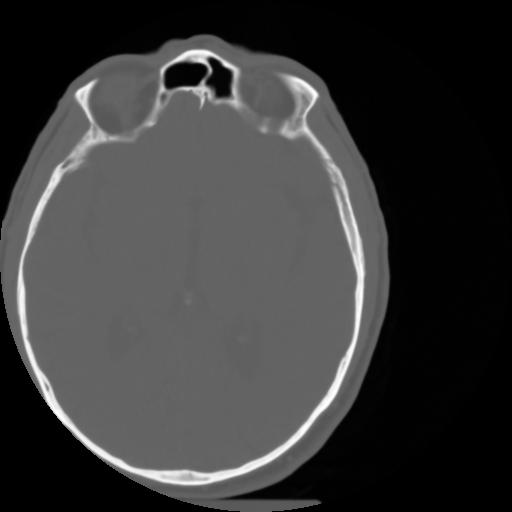

3 CEREBRO,,Axial,3.0,CEREBRO,,